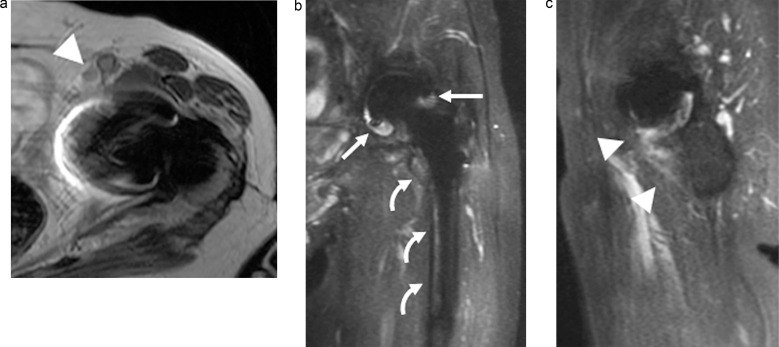

Results: Thirty-seven hip joints in 24 Asian patients (age = 73.9 ± 10.8 years; 18 females) were included. Twelve hip joints (32%) had PJI; seven underwent a surgical intervention. The significant findings for hip PJI included periosteal edema of the acetabulum, intermuscular edema, intramuscular fluid collection, and lymphadenopathy (P < 0.05). In the cases with surgical intervention, the significant findings included capsular distension, capsular thickening, an osteolysis-like pattern of the femur, subcutaneous fluid collection, and lymphadenopathy (P < 0.05). The MRI impressions had high diagnostic significance for both hip PJI cases and those with surgical intervention (P < 0.001). The MRI impression was more significant for hip PJI than the other clinical markers (P < 0.05), while the other clinical markers were more significant in the cases with surgical intervention (P < 0.05).

Conclusion: The significant findings in the hip PJI cases included acetabular periosteal edema, intermuscular edema, intramuscular fluid collection, and lymphadenopathy. The significant findings in the cases with surgical intervention included capsular distention, capsular thickening, a femoral osteolysis-like pattern, subcutaneous fluid collection, and lymphadenopathy. The utilization of MAR MRI demonstrated great diagnostic significance for hip PJI.